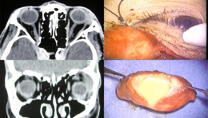

【眼窩腫瘍】ORBITAL TUMORS

cavernous hemangioma 海綿状血管腫、neurilemoma 神経鞘腫

pleomorphic adenoma 多形腺腫

これらの腫瘍につき、視診、細隙灯顕微鏡所見、眼底所見、眼底造影検査、超音波、CT、MRIなど画像の読影を学びます。また、これら代表的疾患の病理像について学習します。

手術には、眼瞼腫瘍の摘出とその再建術、眼窩腫瘍の摘出(場合によっては眼窩骨切り)、眼表面の腫瘍の摘出とその再建術、眼内悪性腫瘍に対する眼球摘出術、腫瘍眼内リンパ腫に対する硝子体手術、涙腺を代表とする生検術、などがあり、担当医として実際の手術に携わります。また、良性の眼瞼腫瘍や霰粒腫の摘出などの習得を目指します。